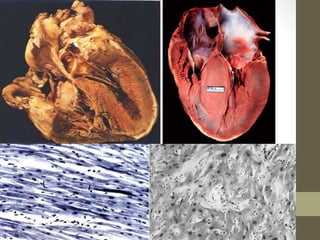

HCM PATHOLOGY

• Gross-

• Hypertrophy – LV/Both

• LV – Ant septum, Post septum, Free wall

• RV – Symmetric

• Histo-

• Disorg muscle bundles – whorled pattern

• Cell-cell orientation lost, Foci of disarray

• Cells – Broad, short, bizzare shape, myofibrillar archit lost

• Interstitial fibrosis

• Result-

• Systolic + Diastolic dysfunction

• Electrical instability